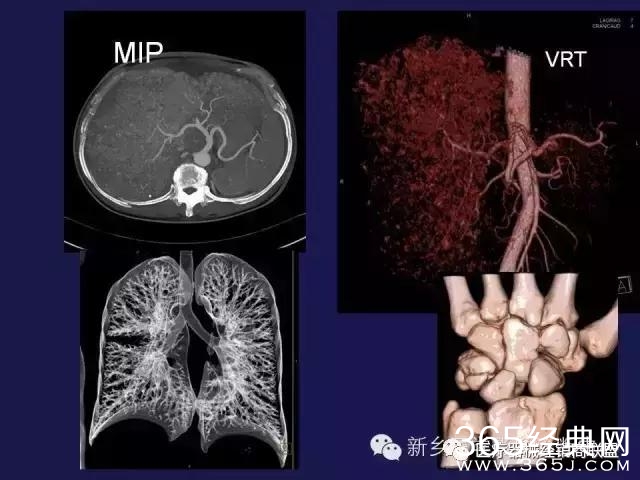

CT、MRI很难?NO,今日我们一起来学习一下如何读CT、MRI!

内行看门道: